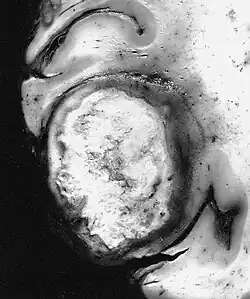

Specialized cells in the central nervous system, such as glial cells, may proliferate abnormally and form gliomas.[6] Glioblastoma is an aggressive form of glioma.[7]